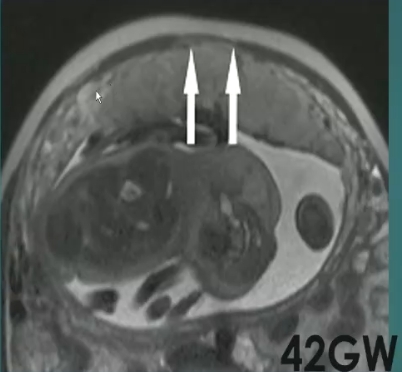

胎盘粘连PA

胎盘穿透PP + 胎盘粘连PA